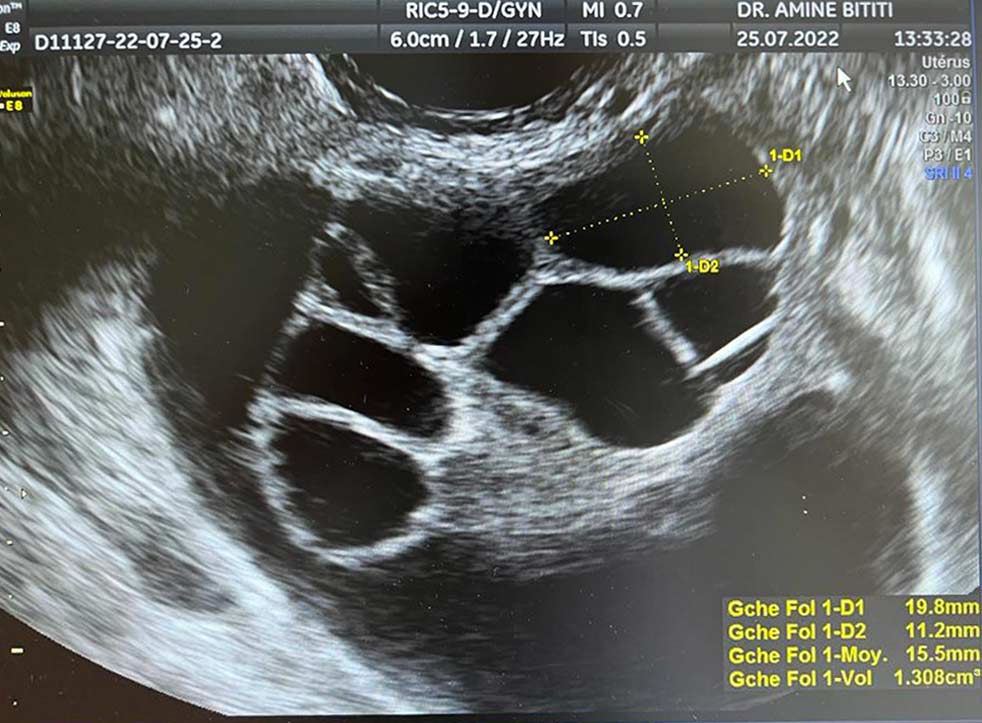

Cette phase consiste à stimuler les ovaires afin de déclencher une ovulation multiple, en administrant à la patiente des hormones similaires à celles qui régulent le cycle menstruel. La stimulation ovarienne est une étape cruciale dans ce type de traitement. L’expérience de notre équipe joue un rôle capital à ce stade. Nous suivons de près cette stimulation par le biais d’échographies et d’analyses de sang. Ces échographies peuvent être réalisées en consultation. Une fois que les follicules ont atteint le nombre et la taille voulus, l’ovulation est déclenchée par voie hormonale. Il faut alors patienter 36 heures avant de procéder à la ponction ovocytaire. Afin de garantir ce suivi exhaustif :